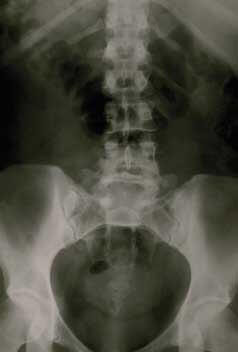

Au niveau du système osseux, un apport œstrogénique naturel sera bénéfique au même titre que de la vitamine D ou K, du calcium ou de l'exercice physique modéré. |